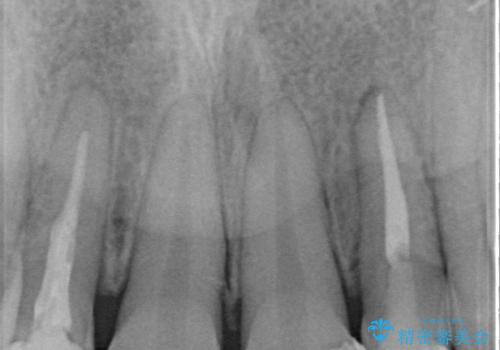

根管治療をしているため、歯の変色が認められます。

特に症状はなく、根管治療のやり直しは希望されなかったため、土台のやり替えから処置をしていくとととしました。